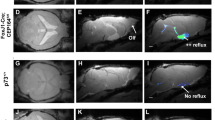

We previously showed ependymal cilia generated a highly organized pattern of flow that can mediate directional transport in the ventral third ventricle (v3V) in the ventral third ventricle (v3V) [10]. To determine the impact of abnormal cilia motion on such cilia-generated transport, explants of the v3V (Fig. 3a) were placed in a medium containing fluorescent beads to allow tracking and mapping of the pattern of fluid flow at the ependymal surface. In wild-type explants, we observed the stereotypic pattern with an inflow stream at the narrow anterior duct and an outflow stream at the posterior duct (Fig. 3b,c, Online Resource 4). Tracing cilia beating orientation showed cilia beating polarity was uniform and aligned with the direction of fluid flow, predicting directional transport of substances along the ependymal surface of the ventricular system (Fig. 3d).

Mispatterned cilia-driven flow blocks fluid transport in Cdkl5 KO mice. a Explant with dorsal (d3V) and ventral third ventricle (v3V, black outline) facing the hypothalamus (HY) and Thalamus (TH) and cilia-generated flow (white arrow) via the anterior (ad) and posterior duct (pd). b Flow maps show tracing of cilia-generated flow. c Tracing of fluorescent beads being transport from into the anterior v3V with the surface flow. d Cilia-beating direction underlying the surface flow. e Time-resolved color-coding of distribution of FITC-dextran following injection into ad. f Flow maps are altered in Cdkl5 KO mice g with an expansive whirl appearing below the anterior duct, h arising from misoriented cilia bundles and i preventing inflow of fluid from the anterior duct clearing the anterioventral surface of v3V

To investigate fluid turnover or clearance in the v3V, a micropipette was used to release a bolus of fluorescein isothiocyanate (FITC)-dextran to mimic freshly delivered CSF. In the wildtype mouse v3V, efficient clearance was observed, with the tracer rapidly spreading from the anterior duct across the anterior and dorsal surface of the v3V (Fig. 3e, Online Resource 5). Analogous analysis of the Cdkl5 KO mouse v3V revealed that the flow map (Fig. 3f,g) showed a circular flow stream or whirl at the anterior duct that blocked cilia-mediated inflow into the v3V (Online Resource 4). Tracing of cilia orientation showed random cilia beating orientation (Fig. 3h). The FITC-dextran did not spread, but stagnated at the site of injection at the anterior duct, demonstrating clearance was effectively blocked (Fig. 3i, Online Resource 5). Further computational modelling of fluid dynamics points to a crucial role for cilia-generated flow rather than bulk flow in mediating clearance in the v3V (Fig. SI2).

Cdkl5 deficiency restricted to multiciliated cells is sufficient to cause flow blockage

As Cdkl5 is expressed not only in the multiciliated ependymal cells but also in neurons and other cell types in the brain, we further investigated whether CDKL5 deficiency in the ependyma alone is sufficient to generate the v3V inflow obstruction seen in the Cdkl5 KO mice. Cdkl5 deletion targeted to the brain ependyma was carried out using a Cdkl5 floxed allele (Cdkl5y/fl) in conjunction with a tamoxifen-inducible FOXJ1 promoter-driven Cre (FOXJ1CreERT) [36, 44]. In the absence of FOXJ1CreERT induction, analysis of the v3V flow map revealed normal patterning of flow in the Cdkl5y/fl mice (Fig. 5a), but following tamoxifen induction of Cre, we observed the same flow blockage at the v3V inflow as seen in the Cdkl5 KO mice (Fig. 5b), confirming CDKL5 deficiency in the ependymal cells alone is sufficient to replicate the v3V inflow blockage seen in the Cdkl5 KO mice.

Cilia-generated flow blockage is a novel type of ciliopathy. a Flow maps of FOXJ1CreERT:Cdkl5y/fl mice shows normal patterning without tamoxifen and b flow whirls with tamoxifen-induced activation of the Cre recombinase. c 4 weeks old FoxJ1± mice show whirl-like flow abnormalities d with normal fluid clearance in wildtype littermates (e) and flow blockage in FoxJ1± KO mice (e). f Five-weeks old wildtype littermates showed occasional twitching of limbs and neck during anesthesia with isoflurane whereas more severe twitching and convulsions were observed in FoxJ1± mice. g This activity persists over a longer duration following sedation